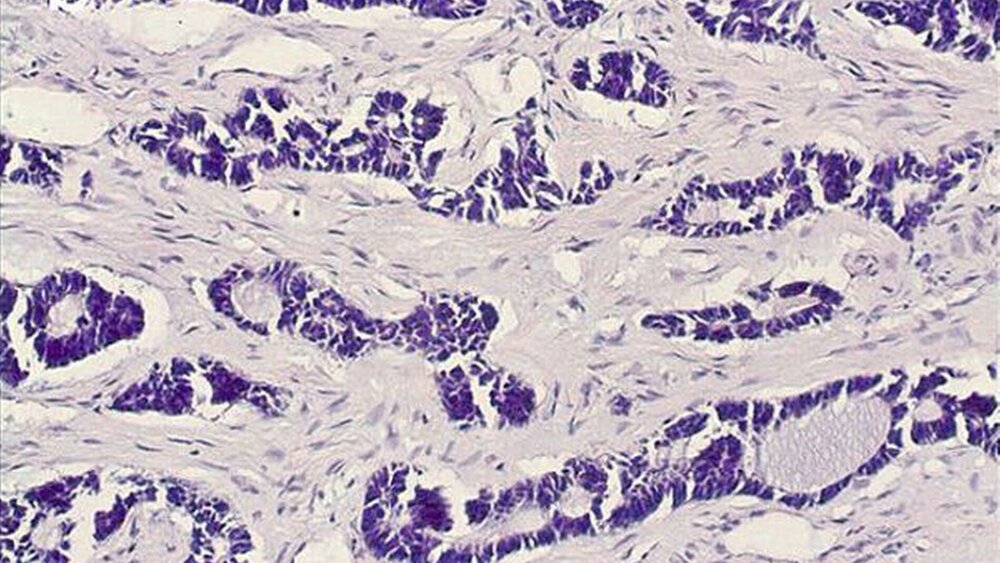

Die abschließende histopathologische Begutachtung diagnostizierte nun mithilfe immunhistochemischer Zusatzuntersuchungen ein von den kleinen Speicheldrüsen ausgehendes adenoid-zystisches Karzinom der linken Kieferhöhle (Abbildung 4). Nach Defektversorgung mittels Obturatorprothese wurde eine postoperative Strahlentherapie eingeleitet.

Histopathologisch ist das adenoid-zystische Karzinom durch das Auftreten duktaler und myoepithelialer Zellen in drei unterschiedliche Wachstumsmuster (kribriform, tubulär oder solide) unterteilt. Wie auch im eigenen Fall dominiert in der Kieferhöhle der kribriforme Subtyp, welcher durch Inseln basaloider epithelialer Zellen charakterisiert ist, die zylindrische, zystische und mit hyalinem Material gefüllte Räume enthalten und an einen „Schweizer Käse“ erinnern [Neville, 2008]. Differenzialdiagnostisch ist das adenoidzystische Karzinom histopathologisch neben weiteren seltenen Speicheldrüsenkarzinomen, wie dem Karzinom im pleomorphen Adenom, dem Speichelgangkarzinom oder dem polymorphen low-grade Adenokarzinom, auch vom sogenannten niedriggradigen sinonasalen nicht intestinalen Adenokarzinom – mitunter schwierig – abzugrenzen, welches nicht den Speicheldrüsen entstammt und in der Regel eine sehr gute Prognose besitzt [Franchi et al., 2005; Cardesa et al., 2006].